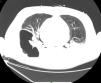

Blood cultures from the recipient were positive for ColR KPC-Kp on day 7 post-operation with the same sensitivity profile as the donor isolate. The surveillance cultures were negative. At this time, the recipient was afebrile and hemodynamically stable, presenting with 26,000cells/mm3 leukocyte count and 6.5mg/dL C-reactive protein (CRP) levels. Double-carbapenems (meropenem 2g 8/8h in a 4-h infusion combined with ertapenem 1g/day, 1h before one of the meropenem doses) and amikacin (15mg/kg once a day) was started. The patient developed pericarditis on day 9 post-operation and required the drainage of 1000mL of exudate; his pericardial fluid cultures were positive for ColR KPC-Kp. The patient underwent a surgical approach to clean the pericardium, requiring a repeated surgery eight days later; a sternum bone fragment collected at this time was positive for ColR KPC-Kp. On day 37 post-operation, he presented with worsening respiratory signs with chest computed tomography exhibiting consolidation with lung fluid levels suggestive of pulmonary cavitation due to necrosis (Fig. 1). This diagnosis was confirmed by histopathology of lung fragments obtained from lobectomy, in which a pulmonary abscess with liquefactive necrosis and necrotizing arteritis were noted. The patient developed septic shock, and antibiotic coverage was extended to linezolid and fluconazole while maintaining the initial treatment regimen for ColR KPC-Kp (double-carbapenem and amikacin). The patient progressed to multiple organ failure and died on day 50 post-transplantation.